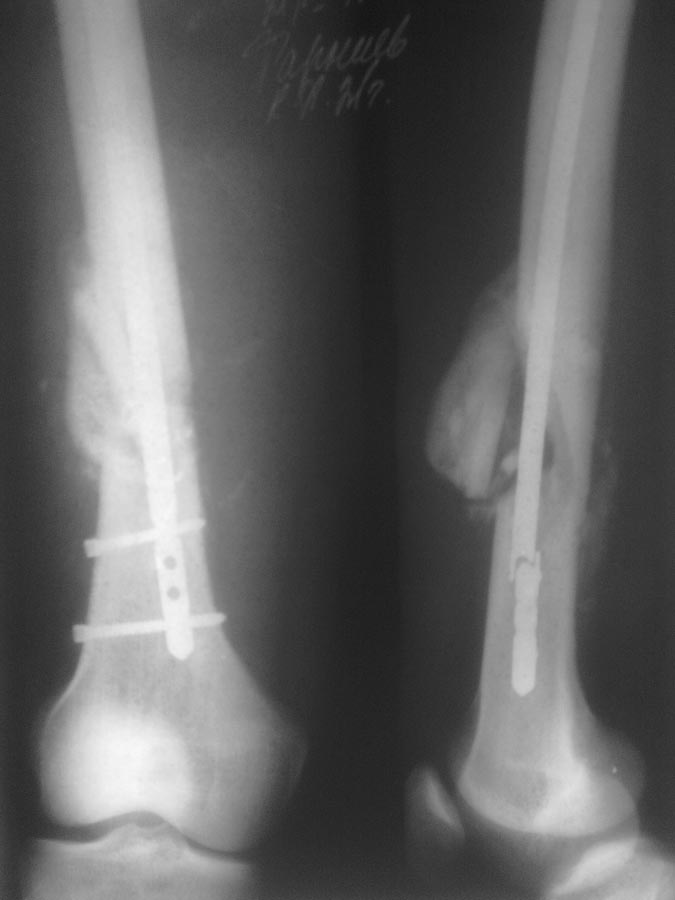

Всем спасибо! Что мы сделали: удалили прокссимальный фрагмент без проблем. Дистальный: через сустав рассверлен канал 13мм. до дистального фрагмента. Который затем удален через тот же канал при помоши загнутой спицы, без особых проблем. Далее ретроградный остеосинтез гвоздем №10.